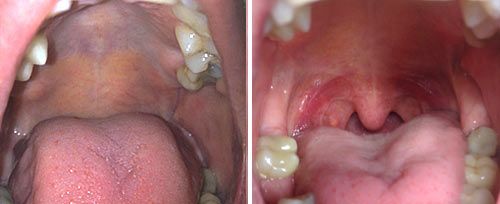

Dr. Hassim’s practice is widely recognized as one of the top laser dentistry centers in South Africa, and is considered among the best worldwide. Combining cutting-edge laser technology with 3D microsurgery, his clinic offers a full range of advanced laser-based procedures, including laser frenectomy, gum depigmentation, minimally invasive laser surgery, and state-of-the-art treatments for gum disease. These procedures ensure precise, pain-free interventions, faster recovery, and improved patient outcomes. This forward-thinking approach places Dr. Hassim and his team at the forefront of advanced dental care, setting a new benchmark for quality and innovation in the industry.

Laser Dentistry

Learn More

Laser dentistry is a minimally invasive treatment option that uses advanced laser technology to perform procedures with greater precision and less discomfort. It is particularly effective for treating gum disease, performing gum recontouring, and promoting faster healing after surgery. The laser also reduces the need for anesthesia in many cases.